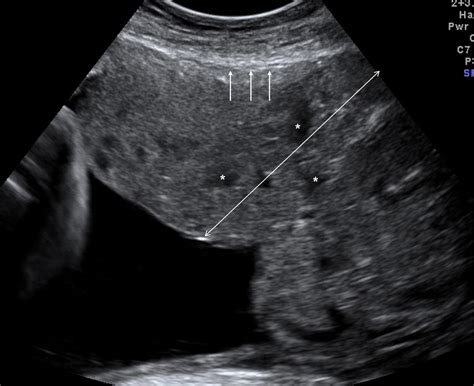

Modern obstetric imaging has made the identification of Placenta Accreta Spectrum much more reliable than in the past. Most cases are identified during the second or third-trimester ultrasound, where specific markers of abnormal placental vascularity are sought by trained sonographers.

Diagnostic Marker Description

Loss of Retroplacental Clear Zone The thin, hypoechoic area between the placenta and the uterus disappears.

Abnormal Placental Lacunae Large, irregular vascular spaces within the placenta that may resemble "Swiss cheese."

Bladder Wall Interruption The interface between the bladder and the uterus appears irregular, suggesting deep invasion.

Exophytic Mass Placental tissue bulging beyond the normal uterine contour.

⚠️ Note: While ultrasounds are highly effective, MRI is often utilized as an adjunct imaging tool to provide better visualization of the depth of invasion, especially in cases where the placenta is located on the posterior wall of the uterus.